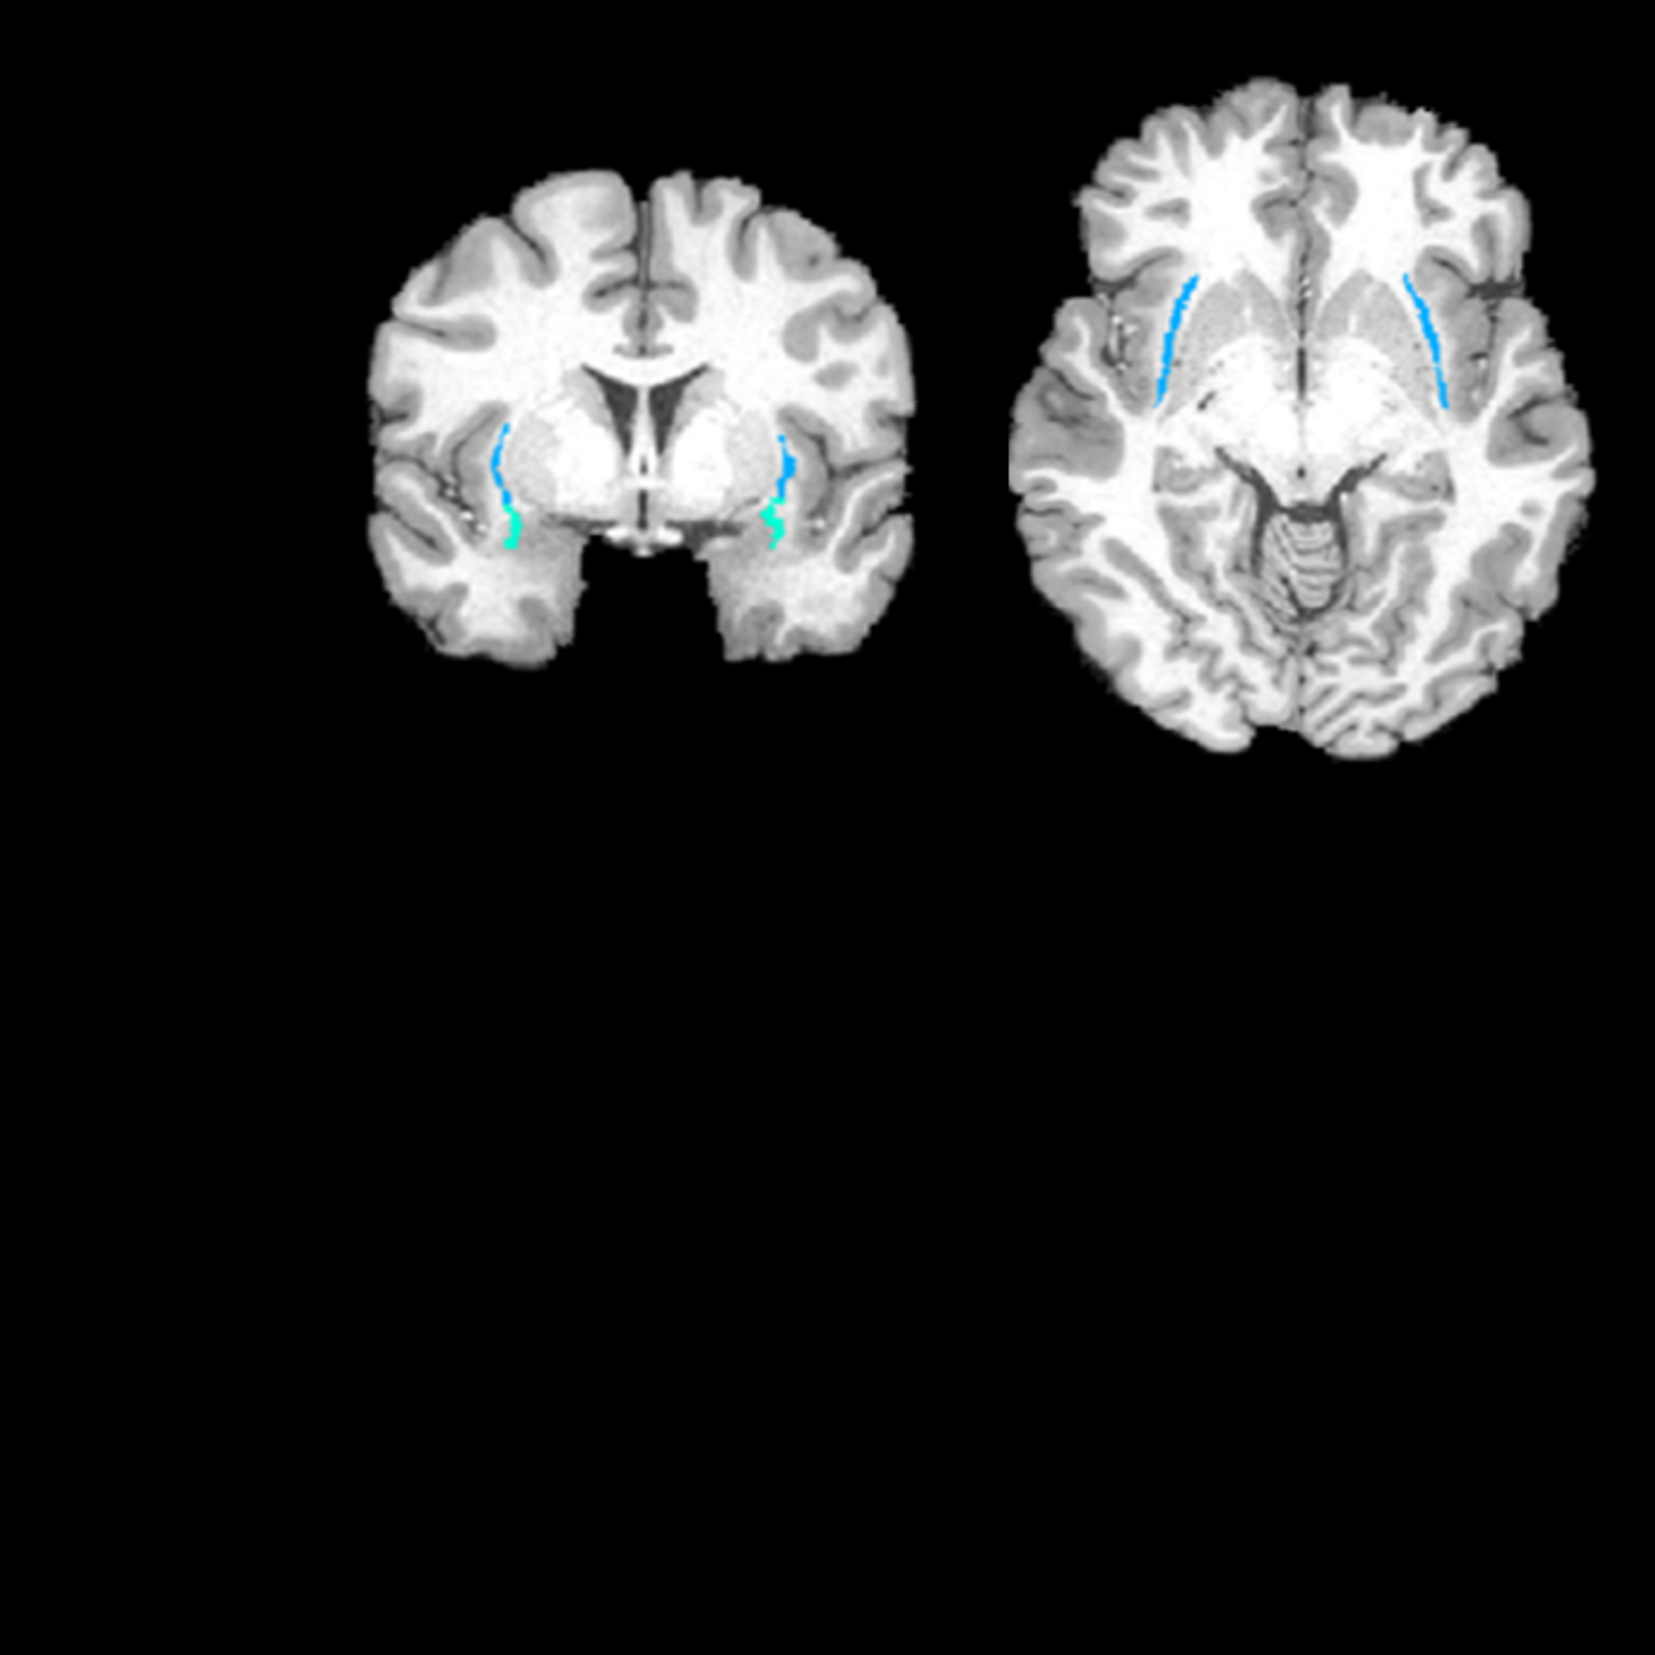

Multimodal Neuroimaging & Computational Neuroscience Research on Human Behaviors & Mental Disorders

Dr. Kang's Cerebral Computing Laboratory is dedicated to studying the brain mechanisms of cognitive/emotional processes and mental disorders. Using Multimodal-Neuroimaging, Psychophysiological, and Computational Methods, we investigate to understand how normal and abnormal brain processes generate complex behaviors. We also aims to develop cutting-edge methods to monitor and modulate neural activities to improve mental functions and psychiatric/neurological symptoms.